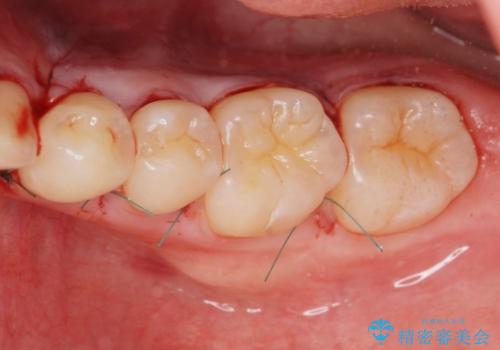

静脈内鎮静麻酔を行い下顎骨隆起切除術を行いました。

骨隆起がなくなり舌が当たるストレスがなくなり大変満足していただけました。

反対側の骨隆起も切除を行う予定です。